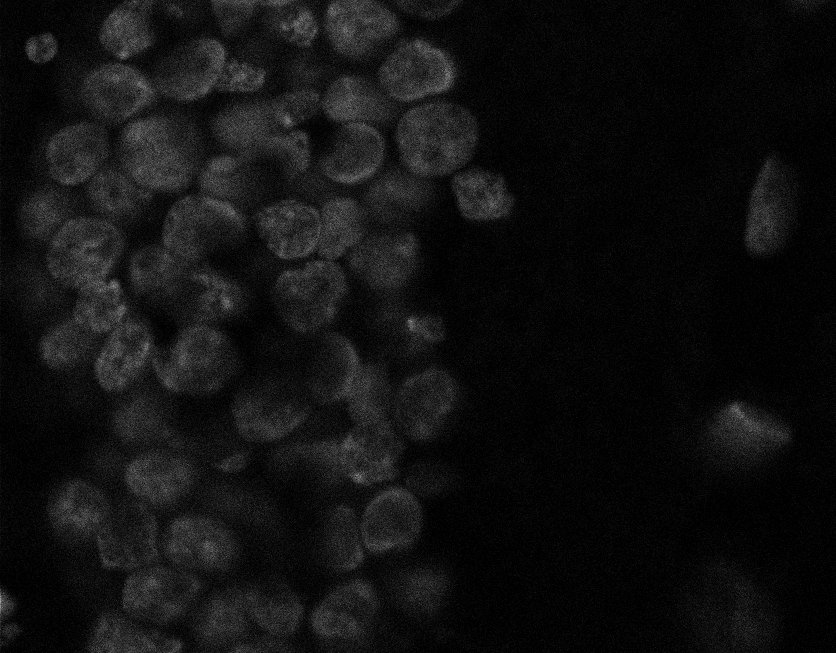

Muscle Cancer